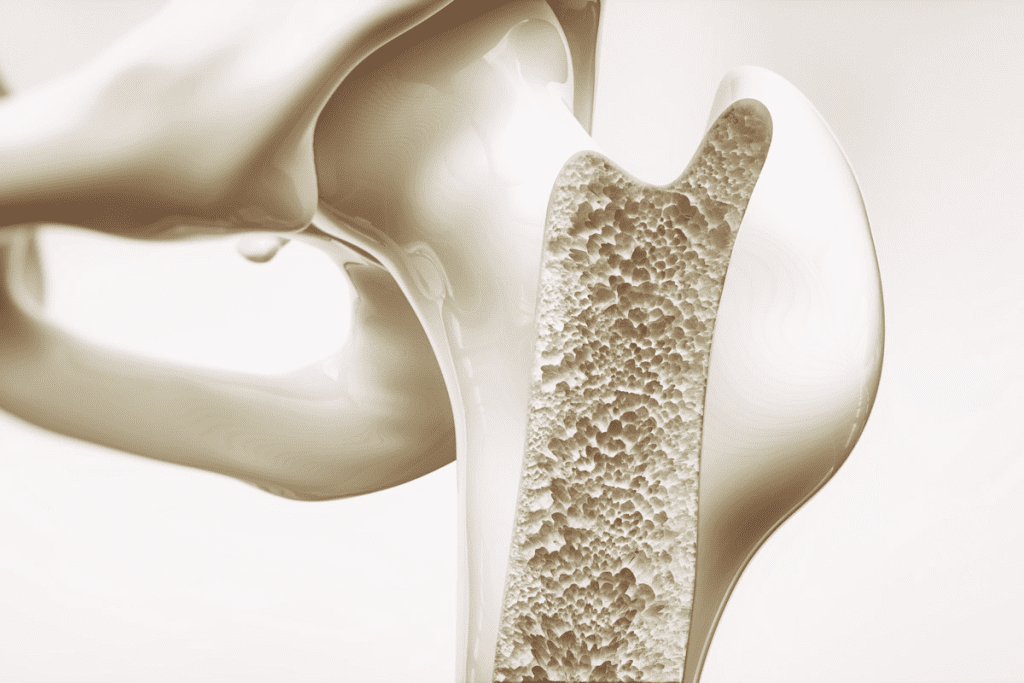

Bright White Spots on Bone Scan: 5 Causes

Bright White Spots on Bone Scan: 5 Causes 5

Bone Fractures: The Most Common Cause of Localized Bright Spots

Bright White Spots on Bone Scan: 5 Causes 6

Bone fractures often show up as bright spots on bone scans. This happens because the body starts to repair the damage. This repair process changes how the bone works, which can be seen on a scan.